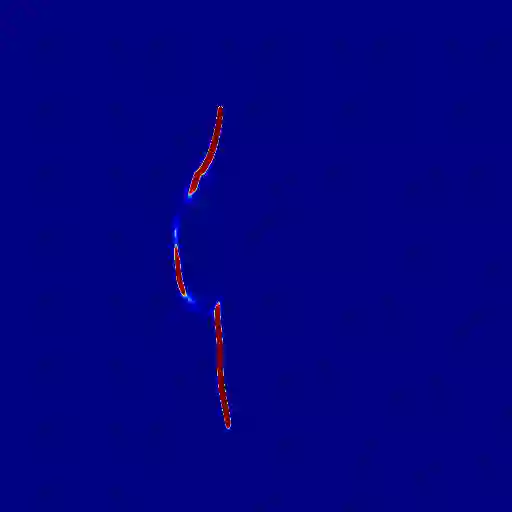

The midline related pathological image features are crucial for evaluating the severity of brain compression caused by stroke or traumatic brain injury (TBI). The automated midline delineation not only improves the assessment and clinical decision making for patients with stroke symptoms or head trauma but also reduces the time of diagnosis. Nevertheless, most of the previous methods model the midline by localizing the anatomical points, which are hard to detect or even missing in severe cases. In this paper, we formulate the brain midline delineation as a segmentation task and propose a three-stage framework. The proposed framework firstly aligns an input CT image into the standard space. Then, the aligned image is processed by a midline detection network (MD-Net) integrated with the CoordConv Layer and Cascade AtrousCconv Module to obtain the probability map. Finally, we formulate the optimal midline selection as a pathfinding problem to solve the problem of the discontinuity of midline delineation. Experimental results show that our proposed framework can achieve superior performance on one in-house dataset and one public dataset.